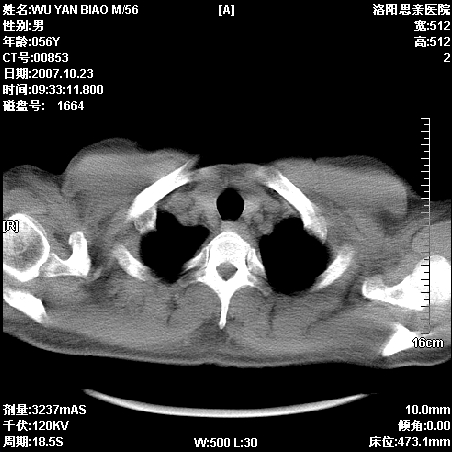

后上纵隔占位,与肺交界清,宽基底附着脊柱,密度均匀,局部骨质无明确改变.

考虑;神经源性肿瘤,---起源交感n链?,不除外肠源性囊肿.

与纵隔关系密切,密度均匀。只能考虑:后纵隔神经原性肿瘤!

后纵隔神经原性肿瘤可能性大,孤立性胸膜间皮瘤待排.

1、病灶在后纵隔脊柱旁沟内,此处是神经原性肿瘤的好发部位

2、病灶边缘光滑整齐,更说明病灶来于纵隔,由于有胸膜的包裹所以才导致这么光滑的边缘

3、病灶内的密度均匀